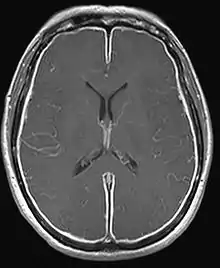

| T1W MRI of the brain demonstrating leptomeningeal enhancement consistent with meningitis | |